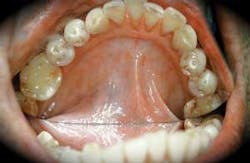

Mr. Patel drinks alcohol several times a week, smokes about half a pack of cigarettes daily, exercises periodically, and eats fast food on a regular basis. You begin the health history and note that Mr. Patel uses a nasal wash, and takes over-the-counter antacids on a regular basis. He tells you that he is slightly overweight and is trying to get into a healthy state. As you begin your intraoral examination, you notice some very noteworthy findings such as tooth wear and a strange white, striated pattern associated with the oral tissues. See Figure 1.

Perioral and intraoral characteristics: Oral submucous fibrosis produces constriction and stiffness of the oral mucosa and may extend into the oral pharynx. Trismus and difficulty in the ability to eat, speak, and swallow are common complaints as the damage to the tissue progresses. Arecoline, a substance found in betel nuts, stimulates the production of collagen by fibroblasts, producing a pale, marblelike appearance in the tissues. Other substances cause the collagen fibers to cross-link, enhancing their strength and inhibiting the body's attempts to break them down. The oral tissue has a leatherlike appearance and consistency. The bands of tissue produce a rippled texture when palpated due to the fibrosis and banding of the tissue structure. See Figure 1.